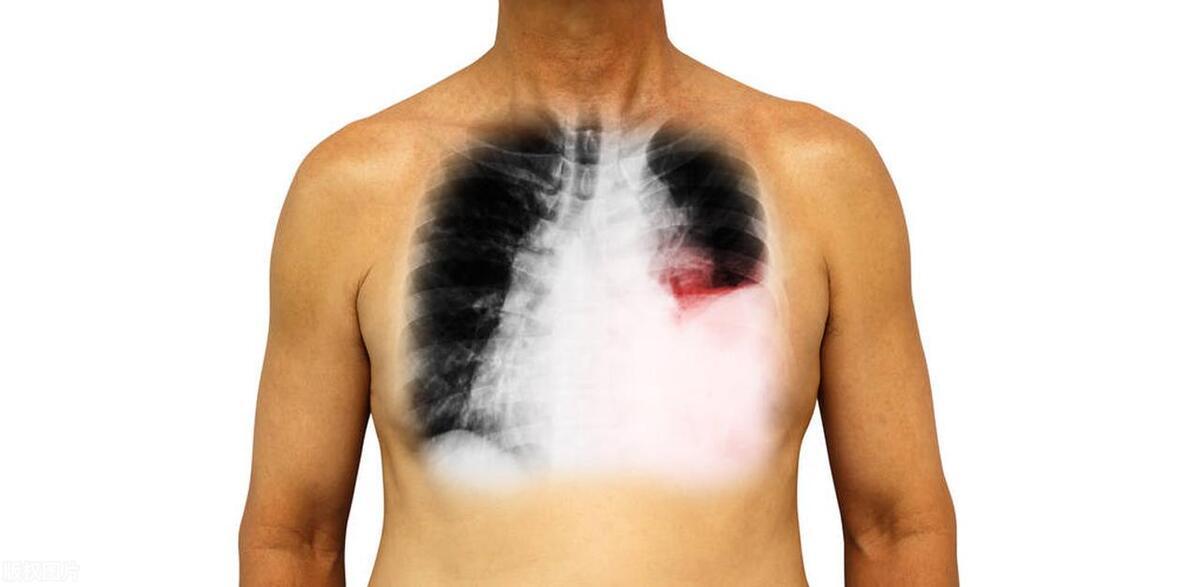

誰也沒想到,李先生竟然會得上這種可怕的病,而且還是肺癌,幸好還是早期。這個消息簡直就是晴天霹靂,一下子就把李先生和他家裏人給擊垮了,他們就像是被扔進了無邊的黑暗裏,痛苦得無法自拔。然而,正是由於及時的察覺和勇敢面對,李先生得以在癌症的早期階段接受治療,爲戰勝病魔贏得了寶貴的時機。

醫生會仔細聽我們講自己的不舒服和身體狀況,然後安排一系列的檢查,這些檢查都是針對我們的情況來定的,非常全面和精準。這可能包括血液生化檢查、影像學檢查(如 X 光、CT、MRI 等)、腫瘤標誌物檢測以及組織活檢等多種手段,以便能夠儘早明確病因,爲後續的治療爭取寶貴的時間和機會。